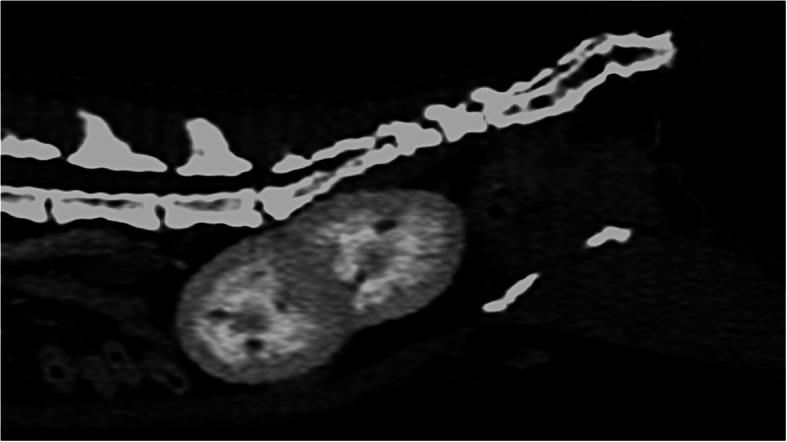

CASE PRESENTATION

An 8-month-old female, domestic cat suffering from chronic diarrhea was referred to the diagnostic imaging unit. The patient showed no other clinical symptoms. An abdominal ultrasonographic examination was performed in order to evaluate the condition of abdominal organs, particularly the gastrointestinal tract. The ultrasound examination showed an ectopic duplex kidney at instead of kidneys in their typical location. Computed tomography (CT) with angiographic phase and excretory urography was requested to evaluate the condition of the kidneys and ureters. The final diagnosis was CFRE, atypical portal vein and coccygeal deformation in an asymptomatic cat with no changes in renal function and normal blood parameters.

病例介绍

一只 8 月龄雌性家猫因慢性腹泻被转诊至影像诊断部门。该猫除腹泻外无其他临床症状。进行了腹部超声检查以评估腹部器官,特别是胃肠道的情况。超声检查显示异位双肾盂,而非在其典型位置的双肾。为评估肾脏和输尿管的情况,请求进行 CT 增强扫描和排泄性尿路造影。最终诊断为 CFRE、非典型门静脉和尾骨畸形,无症状猫无肾功能和血液参数变化。

结论

交叉融合性异位肾是一种罕见的先天性异常,腹部超声检查和 CT 很容易检测到,这允许对肾脏的解剖关系和分泌功能进行更全面的评估。在临床健康的患者中同时发生 CFRE、异常门静脉和脊柱畸形的情况表明,先天性畸形可能同时涉及多个不直接相关的结构和系统,而对血液和尿液参数无明显影响。因此,评估形态和功能变化最有用的工具是影像学诊断,特别是增强 CT。我们的结果表明,在鉴别诊断尾部腹部肿块时应考虑肾融合。